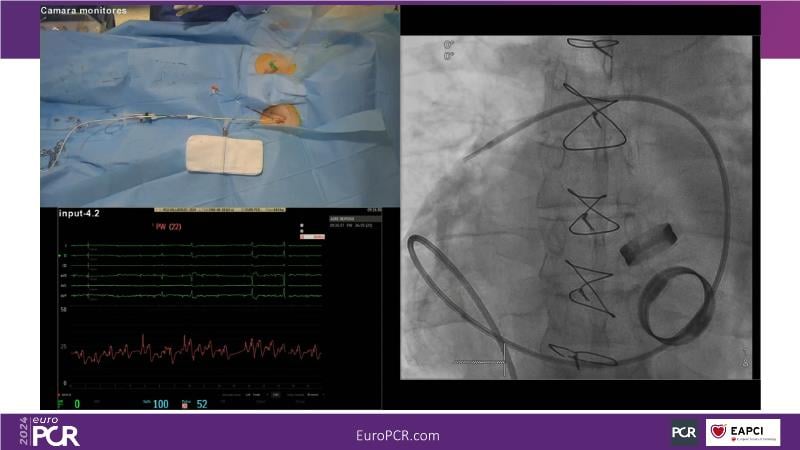

Watch this session to gain comprehensive insights into the use, safety, and efficacy of heterotopic tricuspid valves. Learn to identify ideal candidates with severe tricuspid regurgitation, understand key procedural factors for successful implantation, and receive tips on valve systems and anatomy. The session also includes a recorded TricValve case, discusses the current status of transcatheter tricuspid valve therapies, and explores the placement of heterotopic tricuspid valves in the guidelines.